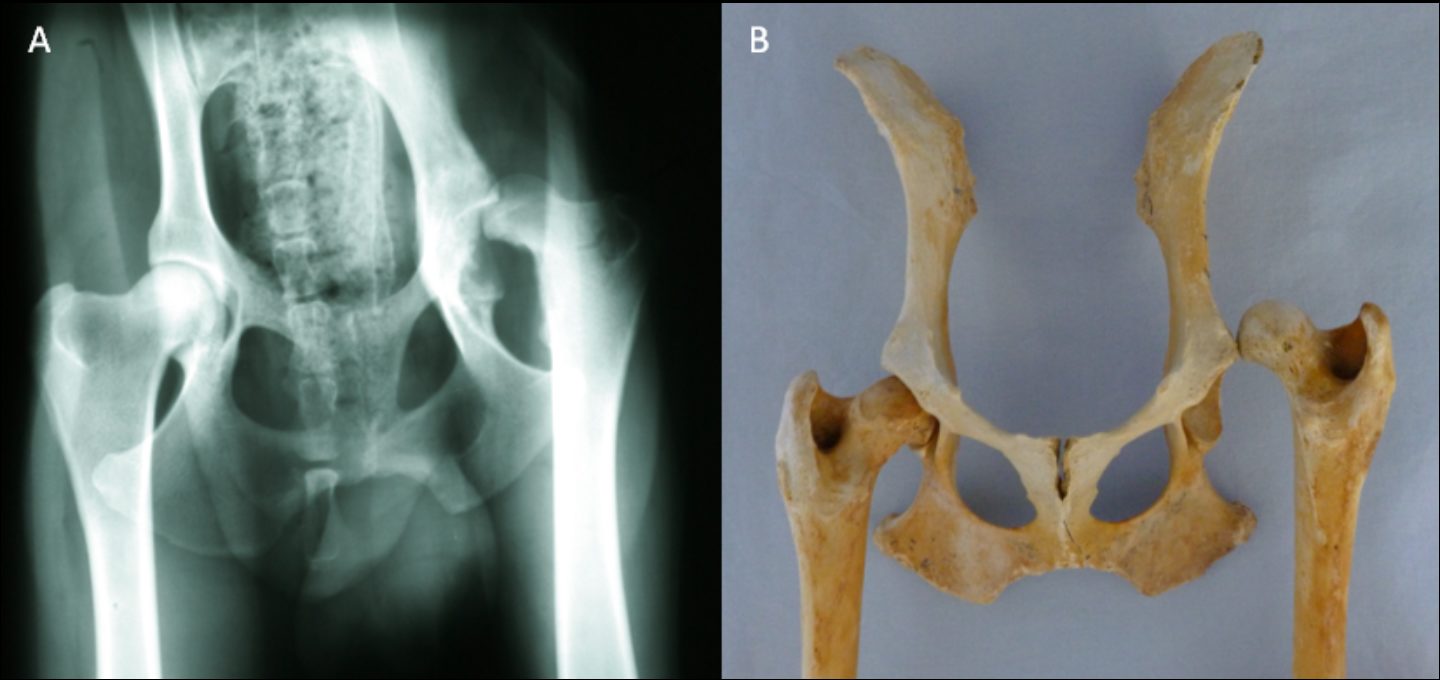

Der künstliche Hüftgelenkersatz wird in der Tiermedizin seit mehr als 30 Jahren zur Behandlung von Hüftgelenkerkrankungen und -Traumata verwendet. Im Grunde werden bei diesem Verfahren Oberschenkelkopf und Pfanne durch eine sog. Oberschenkelkopf- und Pfannenprothese ersetzt. Es gibt verschiedene Modelle von Prothesen. Tylers Oberschenkelkopfprothese besteht aus Titan, die Pfanne besitzt eine Außenhülle ebenfalls aus Titan und eine Innenbeschichtung aus Polyäthylen (s. Abb. 3).